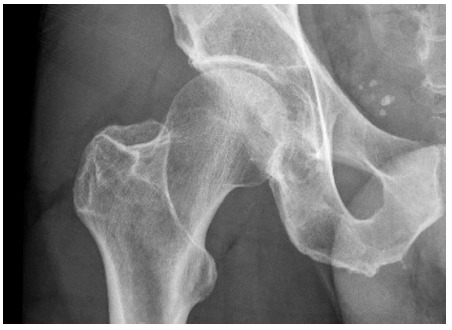

近几十年来,自行车作为一种交通工具和一项竞技运动的参与稳步增加。由跌落和碰撞引起的创伤性损伤发生的相对频繁。髋部和骨盆骨折并不常见,迄今为止没有研究报道其在这项运动中的确切发生率。髋臼特异性损伤的报道甚至更少。我们提出了四个病例,突出了骑自行车者髋臼骨折的隐伏性,并记录了他们的管理和恢复。从自行车上直接跌落到髋侧部导致髋臼骨折的数量相对较高。其中许多可能因x线平片未见发现而被遗漏。因此,在治疗与骑行相关的创伤性损伤时,高度怀疑髋部和骨盆骨折是很重要的。

Cycling participation as a medium of transport and as a competitive sport has steadily increased in recent decades. Traumatic injuries secondary to falls and collisions occur relatively frequently. Fractures of the hip and pelvis are uncommon with no studies to date reporting their exact incidence in this sport. Injuries specific to the acetabulum are reported even less frequently. We present four cases that highlight the insidious nature of acetabular fractures in cyclists and document their management and recovery. The number of acetabular fractures following falls from bicycles directly onto the lateral hip result in a relatively high number of fractures. Many of these may be missed due to the absence of findings on plain x-ray imaging.It is therefore important to have a high index of suspicion for hip and pelvis fractures when treating cycling related traumatic injuries.